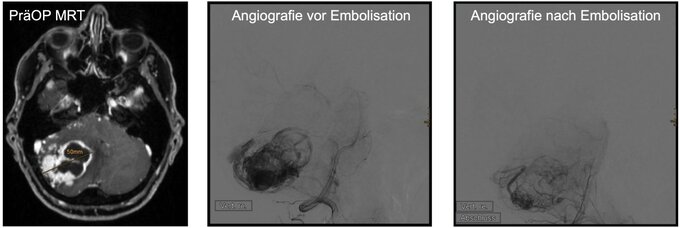

Präoperative Embolisation:

Die soliden Tumoranteile der Hämangioblastome sind stark vaskularisiert. Bei größeren soliden Tumoranteilen (ab 2,5 cm Durchmesser) kann vor der operativen Entfernung eine Embolisation des Tumors sinnhaft sein. Hierbei stellen die Kollegen der Neuroradiologie zunächst im Rahmen einer Angiografie die Tumor-assoziierten Blutgefäße dar (siehe Abbildung) und können diese dann mit speziellen Materialien präzise verschließen (embolisieren). Hierdurch wird die Blutversorgung des Tumors entscheidend reduziert. Die operative Resektion des Tumors findet in den ersten drei Tagen nach der Embolisation statt.